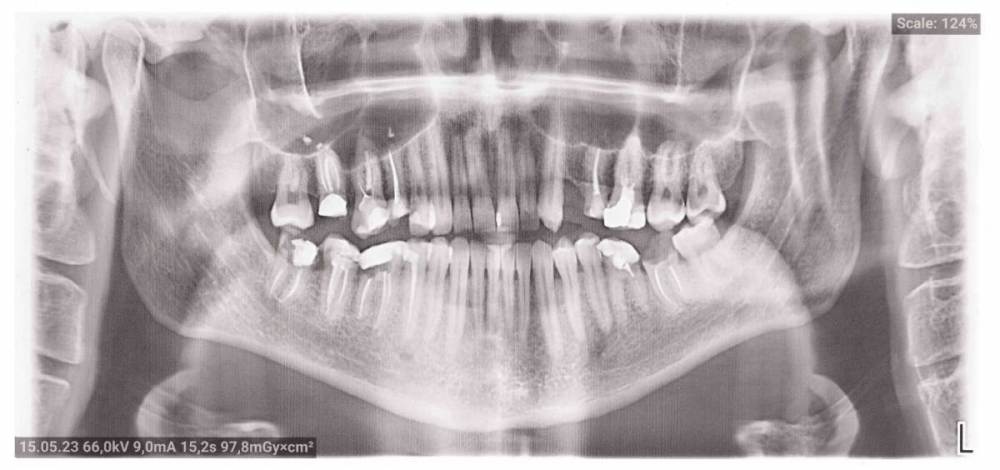

Еще общий снимок.

панорамный-150523.jpg

Добрый день. Я обратился к врачу с острой болью 2 мая 2023 года. У меня там откололся кусок зуба (6 правый нижний) и он болел. (Там в 2015 году ставили пломбу, но нервы не удаляли.) 2 мая мне положили безмышьяковую пасту девит С под дентин. Правда до конца нервы не убились и мне сделали 10 мая еще анестезию и пломбировку 3 каналов, но зуб до сих пор болит. И между 6 и 7 зубом болит и примерно на 1 см ниже зуба челюсть болит и слегка опухла. 13 мая повторно ходил в клинику, но там сказали, что это скоро пройдет. А может там плохо выполнили пломбировку каналов и часть нерва осталось?

возможное есть доп каналы, я бы советовал сделать компьютерную томографию и посмотреть вместе с Вашим доктором